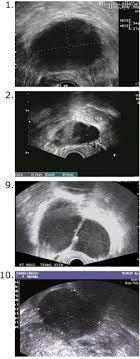

Diagnostics Free Full Text Differential Diagnosis Of Endometriosis By Ultrasound A Rising Challenge Html from www.mdpi.com It is unclear what causes ovarian cancer, but risk factors include a family history of the condition and mutations in certain genes. While there are similarities between endometriosis and ovarian cancer, difference are apparent as well. Ovarian cancer can indeed be mistaken for endometriosis. Answer from tatnai burnett, m.d. I am 42 years old, and have been experiencing perimenopausal symptoms for about 4 years. Ovarian cysts are often identified when an ultrasound examination is performed for another reason. These are the eight conditions that endometriosis is often mistaken for. Many other symptoms can have similar symptoms such as endometriosis, fibroids uterine myomas, gastrointestinal conditions such as colitis, ibs, diverticulosis and benign ovarian cysts. what makes the situation more vexing is if the patient has only a few symptoms.

Ovarian cysts are often identified when an ultrasound examination is performed for another reason.